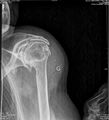

- Différentes lésion labrales post.jpg Alexandre.laedermann

19:53, 26 January 2020

1,918 × 454; 739 KB